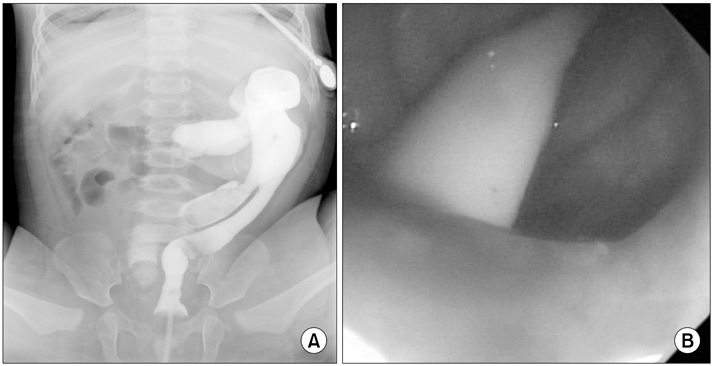

Fig. 1). Under general anesthesia, a small opening located posterior to and near the vagina at vestibule was found. The structure that had been misdiagnosed as a fistula based on the colon study was not present. The patient had a normally sited anus, an anterior ectopic anus, and a double vagina (

Fig. 2). A catheter was inserted through the ectopic anus, and an intraoperative contrast study and sigmoidoscopy were performed. A parallel tubular duplication with a common wall was found. The common wall extended 5 cm from the anal verge to the sigmoid colon and then 20 cm to the level of the proximal sigmoid colon. Proximally, the anterior duplication and normal colon merged and formed a normal colon. Because most of the stool moved through the anterior duplication and because the diameter of the anterior duplication was larger than that of the normally located colon (

Fig. 2Examination under general anesthesia revealed a normal anus, an anterior anorectal duplication (catheter-inserted state), and duplicate vaginal openings.

Fig. 3Intraoperative findings. (A) The intraoperative contrast study revealed that the contrast injected via the anterior anorectal duplication filled the normal colon and rectum and that there was a connection between the duplication and the normal colon at the level of the proximal sigmoid colon. (B) Intraoperative sigmoidoscopy at the merging point revealed that a catheter inserted via the anterior anorectal duplication could be observed by a scope inserted via the normal anus.